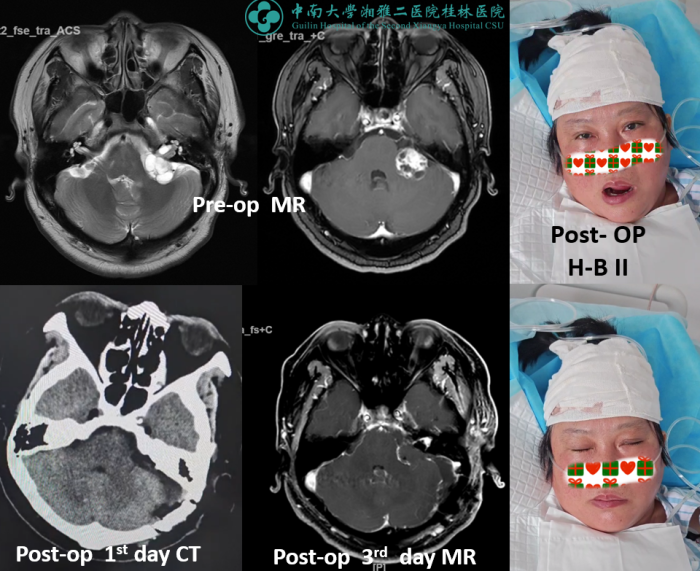

近日,中南大学湘雅二医院桂林医院神经外科团队连续成功完成两例Koos 4级的大型听神经瘤显微外科切除手术。

凭借严谨细致的术前规划、术中电生理的精准监测与显微手术的高超技艺,中南大学湘雅二医院桂林医院神经外科团队不仅成功完成手术,还实现了患者术后良好的功能保留。目前患者恢复良好,已于近日出院。

中南大学湘雅二医院桂林医院神经外科团队在手术前,基于患者的影像学结果和身体状况,制定了精准的个性化手术方案。由于两位大型听神经瘤患者就诊时,均为听力丧失状态,听神经功能无法恢复。为了最大限度地保留面神经功能,减轻脑干激惹影响,手术采用了显微神经外科技术,并结合术中神经监测,实现精准分离,保护关键神经血管结构,确保肿瘤尽可能彻底切除的同时,对其他神经功能影响降到最低。